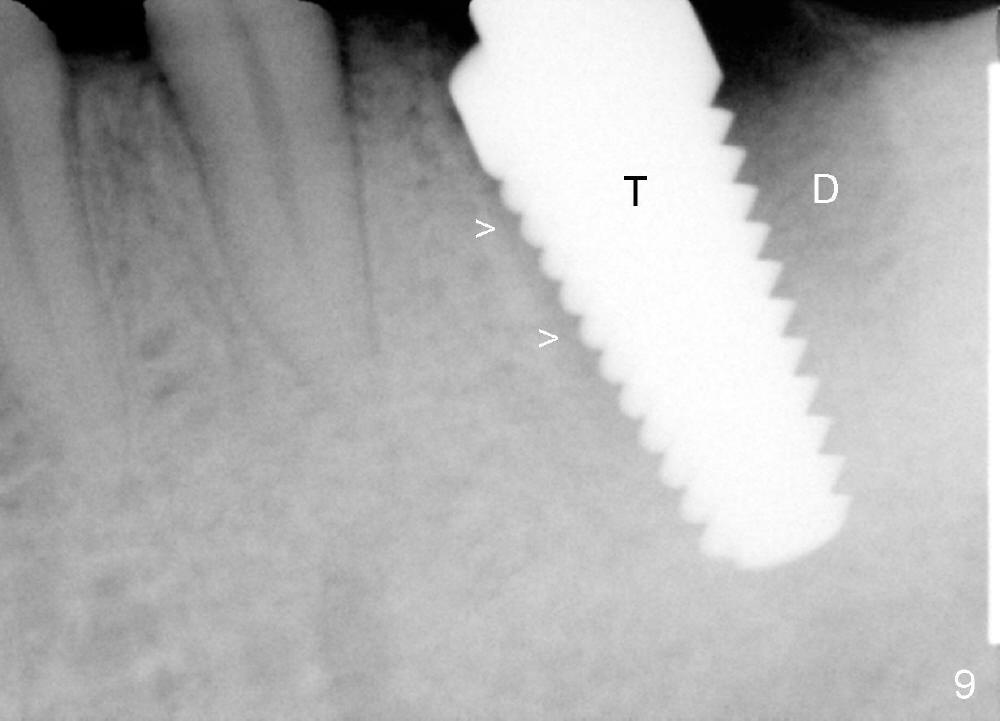

The implant is placed in the mesial socket (Fig.9 T: 7x17 mm tap): the mesial space is being obliterated (>), while the distal one (D) should have been filled with bone graft and the overlying gingiva is approximated with suture (Fig.6). Bone graft is not placed, because graft may increase chance of infection. In fact this assumption is wrong. First, when the tooth #8 is extracted a few months later, bone graft is done with immediate implant. No infection occurs. Second, no bone graft in #18 distal socket leads to gingival recession, as shown below.